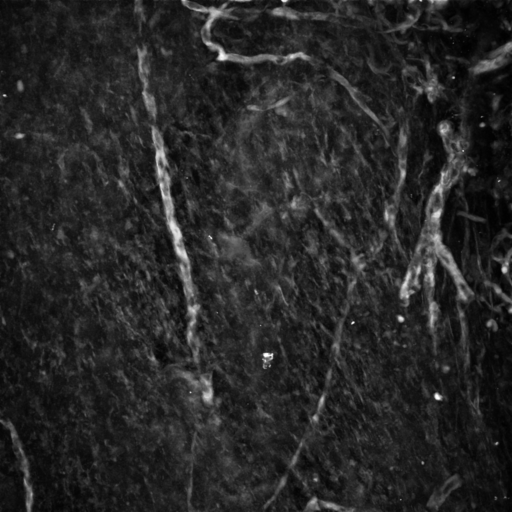

Imaging by 2-photon microscopy a red fluorescent protein approx 200 um inside mouse bone. Original images looked very blurry. Or you judge.

Single optical section original image followed by after 90% of 33 pixel neighborhood median filtered image subtracted. Original image was 2X shown here (1024 X 1024 voxels):